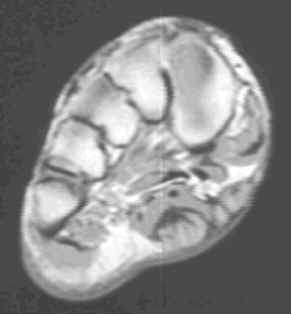

Characterized by nodular or poorly defined aggregates of mature to somewhat immature fibroblasts dispersed throughout dense collagen, causing irregular or nodular subcutaneous thickening of the plantar fascia. On MR, this appears as a nodular thickening of the plantar aponeurosis, which has low to intermediate signal intensity on both T1 and T2W images. Central increased signal intensity may be present.

62-year-old male with nodular thickening of the plantar fascia. This has intermediate signal on T1W and hyperintense signal on T2, proton density and Stir weighted images. These are atypical signal characteristics of plantar fibromatosis.